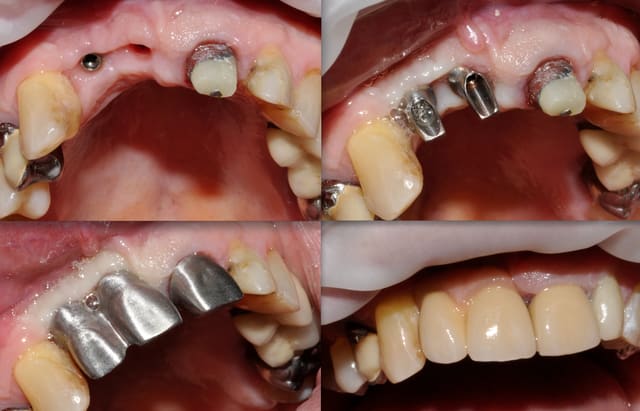

patient désirant un sourire plus sympa, j'en suis au stade prothèse, et j'aimerais faire une fausse gencive ceram (ou résine), un peu dans le style de l'article de Richard ABULIUS paru dans dentoscope n°62.

choix du matériau concernant adaptabilité, l'hygiène, et le respect de la teinte sachant que la partie fausse gencive concernera 21 à 14 environ (je garde 22/23/24/25), bridge sur implant, la longueur des dents sera à peu près ce qui est sur les photos 2 et 3 .

photos de la bouche au départ

100 4442r ro8hie - Eugenol

100 4473r hvl501 - Eugenol

100 4446 o2upvt - Eugenol